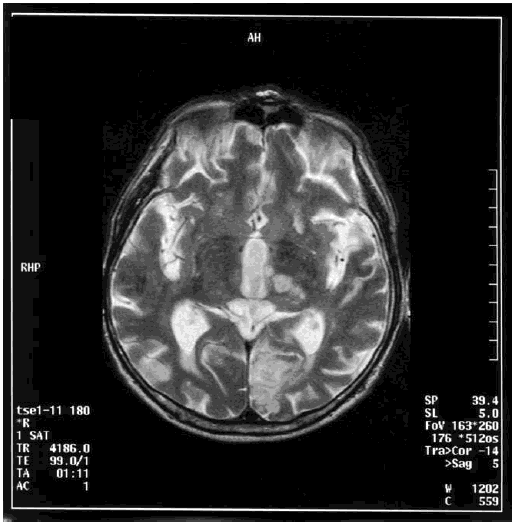

При разрыве аневризмы передней соединительной артерии, сопровождающемся субарахноидальным или паренхиматозным кровоизлиянием и вазоспазмом в системе передних мозговых артерий, развиваются выраженные когнитивные расстройства: нарушение памяти на фоне общих аффективных изменений личности с явлениями расторможенности и нарушением контроля над протеканием психических процессов, нередко с дезориентировкой во времени и пространстве и конфабуляциями [114]. Именно такая клиническая картина наблюдалась у пациента с массивным субарахноидальным кровоизлиянием с разрывом крупной мешотчатой аневризмы передней соединительной артерии, КТ-ангиография которого представлена на рис. 6.2.

Иллюстрация к книге — Деменция. Диагностика и лечение [i_005.jpg]

Рис. 6.2. КТ-ангиография с картиной массивного субарахноидального кровоизлияния у пациента с аневризмой передней соединительной артерии